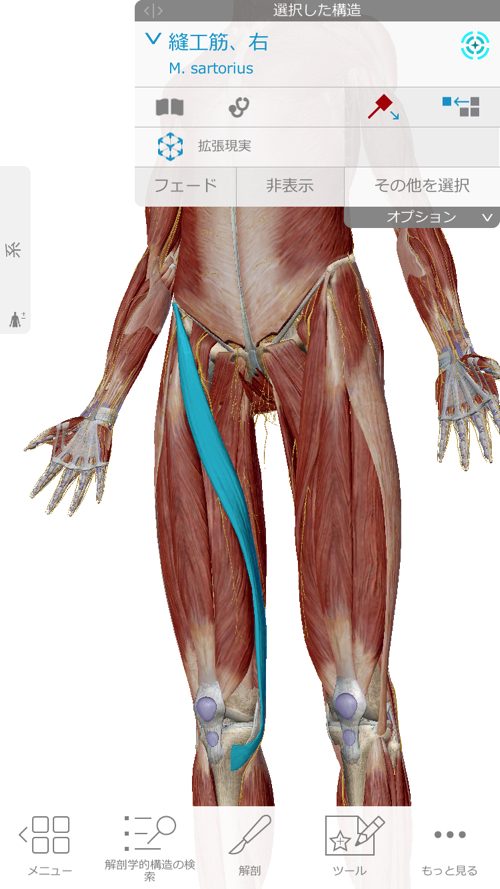

まずはここの縫工筋を緩めて 膝に余裕を作ります。

同時にここの腸骨筋なども緩めて鼠径部から膝に余裕を作ります。